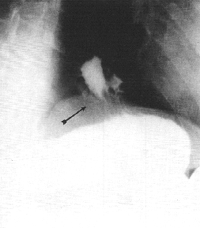

Case 32.4. C.W., 70 year old female, was a known case of hiatus hernia and peptic oesophagitis. Radiographic examination showed irregular narrowing of the distal oesophagus, a sliding hiatus hernia and free gastro-oesophageal reflux (Fig. 32.4A). There was constant contraction of the pyloric sphincteric cylinder, with absence of cyclical activity; the partially contracted cylinder fixed the pyloric aperture in the open position (Fig. 32.4B). Intramuscular administration of an antispasmodic produced no change. Endoscopy confirmed the hiatus hernia with chronic, non-specific oesophagitis. No structural abnormality was seen in the remainder of the stomach, the pyloric region and duodenum.

A![]() | |

B | |

| Fig. 32.4 A. Case C.W. Sliding hiatus hernia with free gastro-oesophageal reflux (arrow). B. Case C.W. Constant contraction of pyloric sphincteric cylinder. Pyloric aperture "fixed" in open position | |